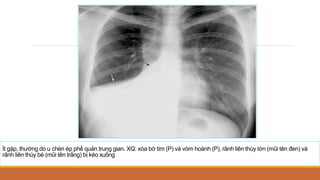

Ít gặp, thường do u chèn ép phế quản trung gian. XQ: xóa bờ tim (P) và vòm hoành (P), rãnh liên thùy lớn (mũi tên đen) và

rãnh liên thùy bé (mũi tên trắng) bị kéo xuống